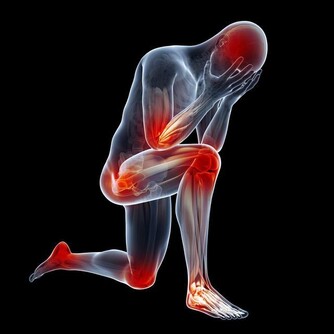

免疫力下降,有哪些症狀?

想要知道自己免疫力好不好,不妨簡單測試一下。如果以下表現佔了一半,該敲醒“警鐘”了~

免疫力低下,容易生病怎麼辦? 不妨做4件事,提升免疫力

1、經常感冒

• 免疫力下降的人,最直觀的表現就是容易感冒發燒,尤其在季節交替、溫度驟變之時,更為高發;

• 一年中感冒次數超過3次,且病程一般有7天甚至10天以上;

• 感冒還反反复复,即康復後,過幾天又發作了。

2、身體疲勞

經常感到全身疲憊,稍微做點事就會覺得累;每天即便睡眠充足,睡眠時間超過9個小時,但仍覺得困倦,精神不振,還容易分神。